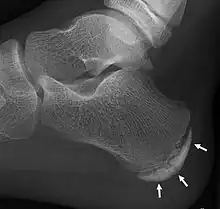

X-ray of the foot of an 11-year-old child, showing sclerosis and fragmentation of the calcaneal apophysis. This is a sign of low sensitivity and specificity of Sever's disease, because those with Sever's disease may not have it, and this appearance is also present in feet without pain.[1] | |